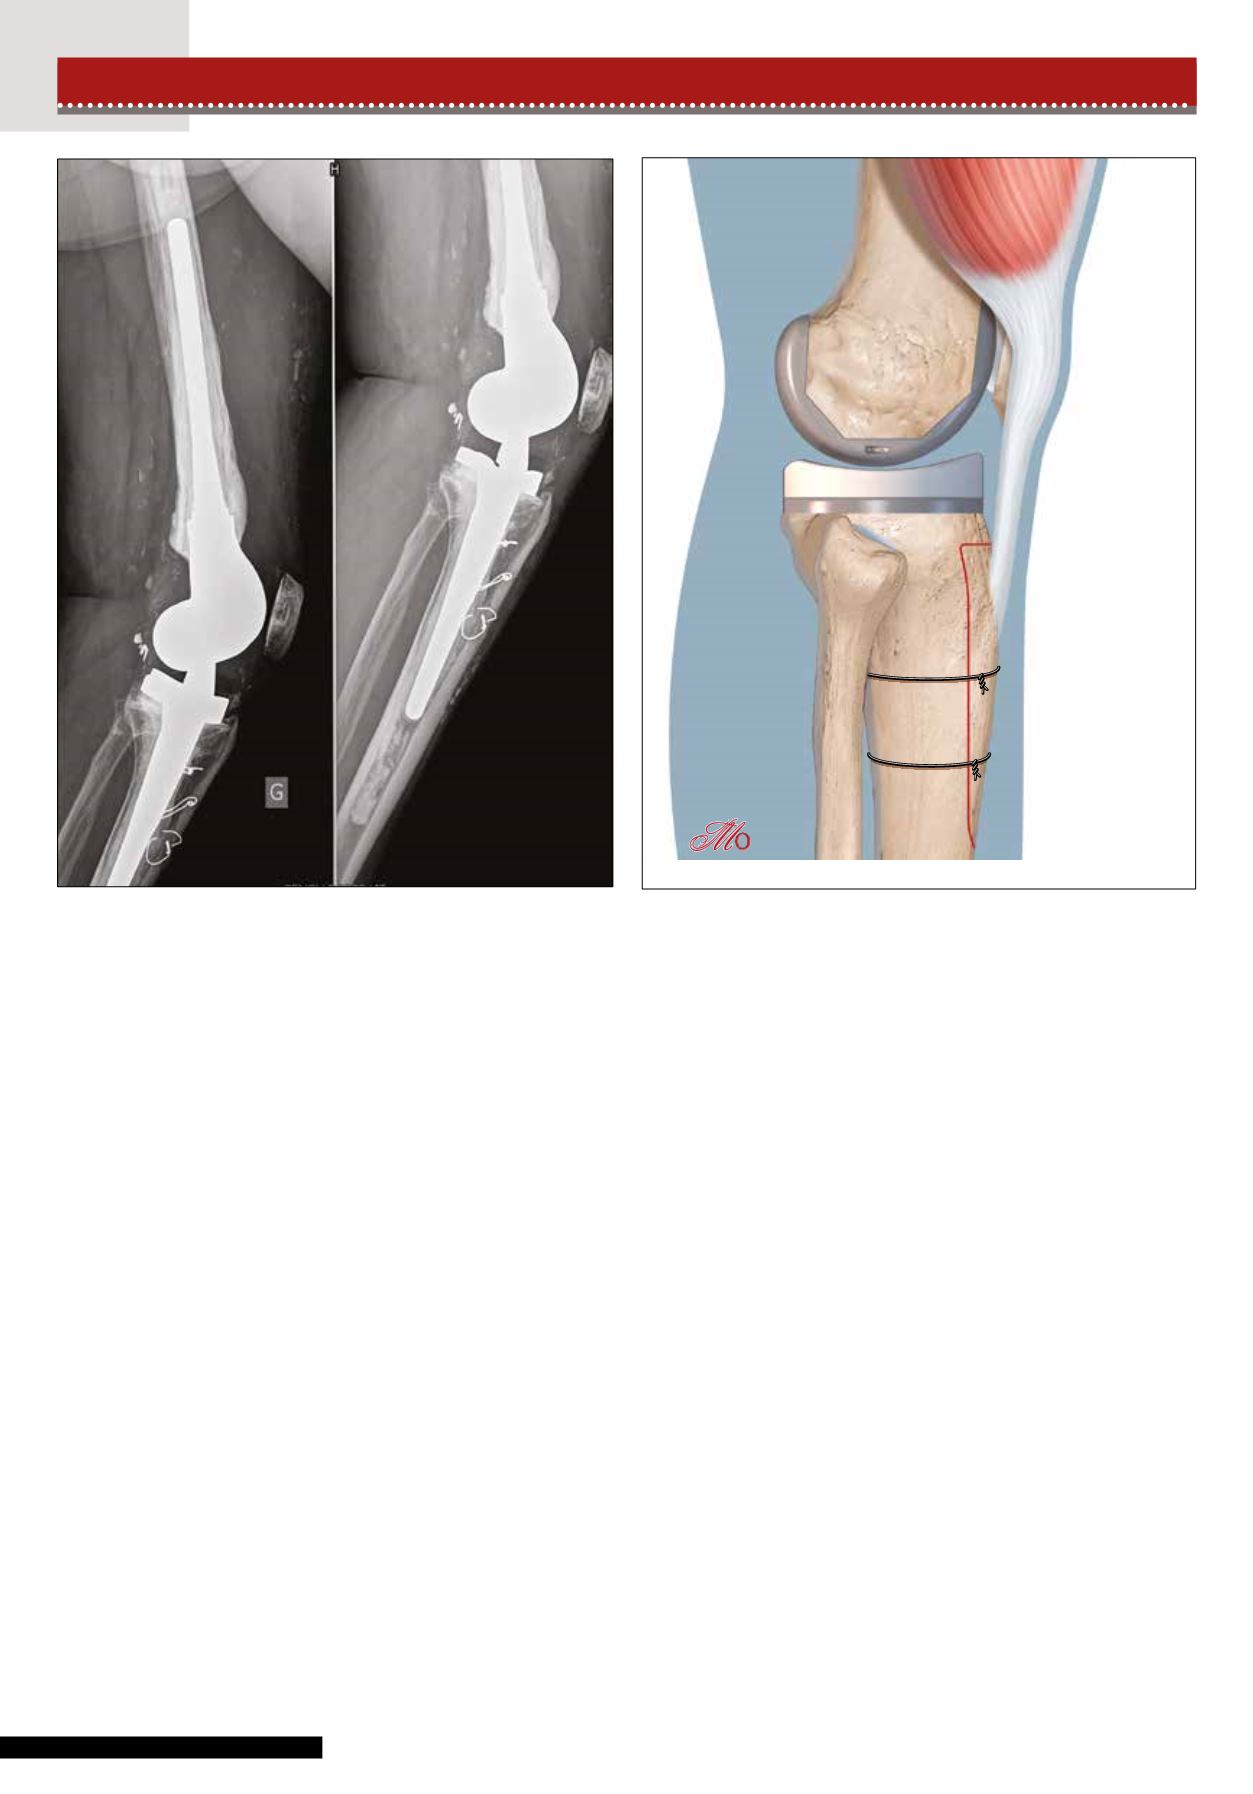

Figure 4 : fixation de la TTA par cerclages métalliques transosseux.

Figure 5 : fixation de la TTA par cerclages circonférentiels.